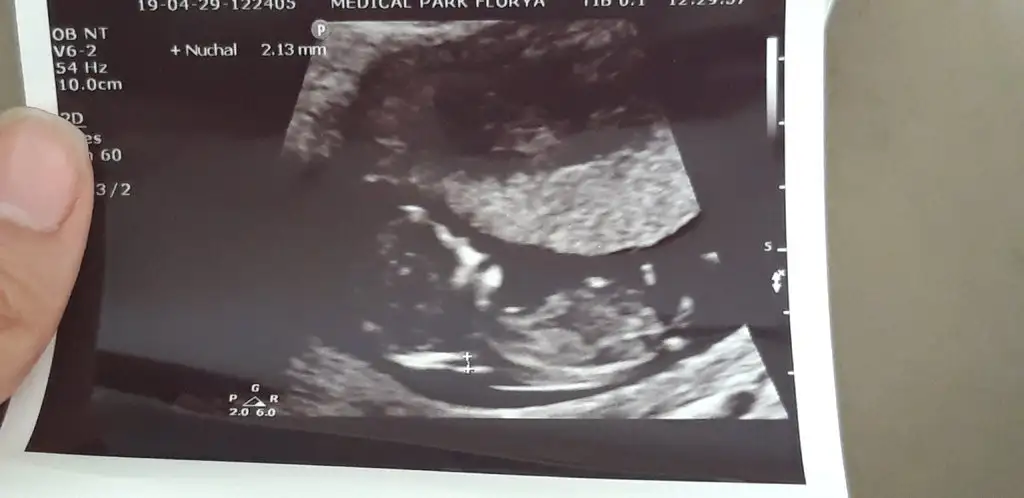

Kizlar dondüm muayeneden. 12+0 gorunuyor minigim. Boyu 5 bucuk cm olmus o yuzden ense kalinligi ve burun kemigine de bakti doktorum cok netti burnu hersey gayet guzel 1.33 mm ciktı ense kalinligi. Riski yok cok saglikli kan ver kan sonucuna da bakayim dedi kan verdim ve ciktim. Ama doktor ultrasonda ölcüm yapana kadar akla karayi secti 1 saniye durmadi zipliyor yuzustu yatior geri arkasini donuyor bu kez sıkılıp sirt ustu yatiyor o kucucuk yerde poposu bir yeryuzu gormedi . Doktor da masallah bu ne kadar hareketli bir bebekmis boyle dedi.cinsiyetini sordum simdiye kadar hic 14.haftadan once soylemedim kimseye prensip ! dedi bir dahaki randevunda soylerim dedi . Birdahaki randevumda 1 ay sonra çatlarim heralde